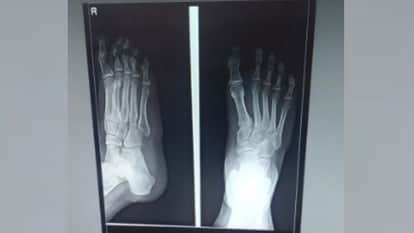

प्रतीकात्मक तस्वीर।

- फोटो : amar ujala